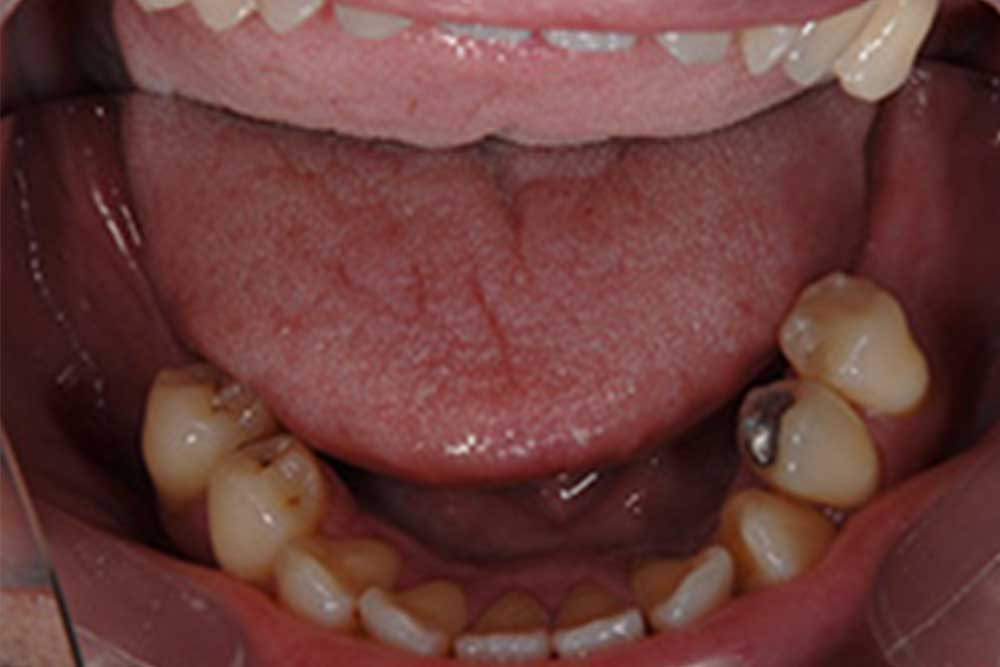

治療前

奥歯で物が噛めないとのことで来院。骨量も特に問題なく骨移植なくインプラントができました。違和感もなく、なんでも噛めるようになったということでした。

| 年齢・性別 | 55歳 男性 |

| 治療費 | 1,210,000円(税込) |

| 治療期間 | 5ヵ月 |

| 通院回数 | 7回 |

| リスク・注意点 | 定期検診を継続するとインプラントは維持できますので、途切れずに通うことが大事です。ご自身の歯も同様ですが、日々のブラッシングにより、歯垢をしっかり取り除くことで、トラブルが減少しますが、当然に怠ってしまうと歯周病で抜けるリスクがありますので注意が必要です。 |